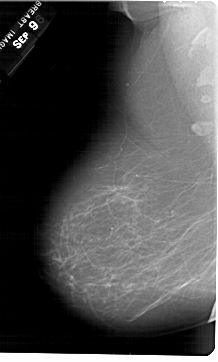

A_1354_1.RIGHT_MLO

RIGHT_MLO LINES 6721 PIXELS_PER_LINE 4246 BITS_PER_PIXEL 12 RESOLUTION 43.5 OVERLAY